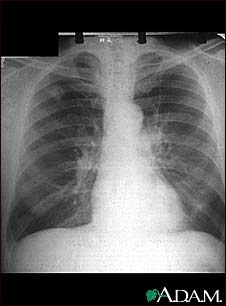

Adenocarcinoma - chest X-ray

This chest x-ray shows adenocarcinoma of the lung. There is a rounded light spot in the right upper lung (left side of the picture) at the level of the second rib. The light spot has irregular and poorly defined borders and is not uniform in density. Diseases that may cause this type of x-ray result would be tuberculous or fungal granuloma, and malignant or benign tumors.